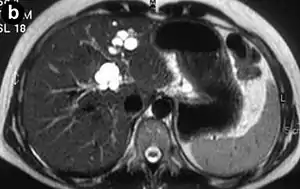

Doença de Caroli é um distúrbio hereditário raro caracterizado por dilatação cística (ou ectasia) dos ductos biliares no fígado. Existem dois padrões de doença de Caroli: a doença focal ou simples consiste em ductos biliares anormalmente alargados que afetam uma porção isolada do fígado. A segunda forma é mais difusa e, quando associada à hipertensão portal e fibrose hepática congênita, é frequentemente chamada de "síndrome de Caroli".[2] As diferenças subjacentes entre os dois tipos não são bem compreendidas. Também está associada a insuficiência hepática e doença renal policística. A doença afeta cerca de uma em 1 milhão de pessoas, com mais casos relatados de síndrome de Caroli do que de doença de Caroli.[3]

É distinta de outras doenças que causam dilatação ductal causada por obstrução, por não ser um dos muitos derivados do cisto de colédoco.[2]